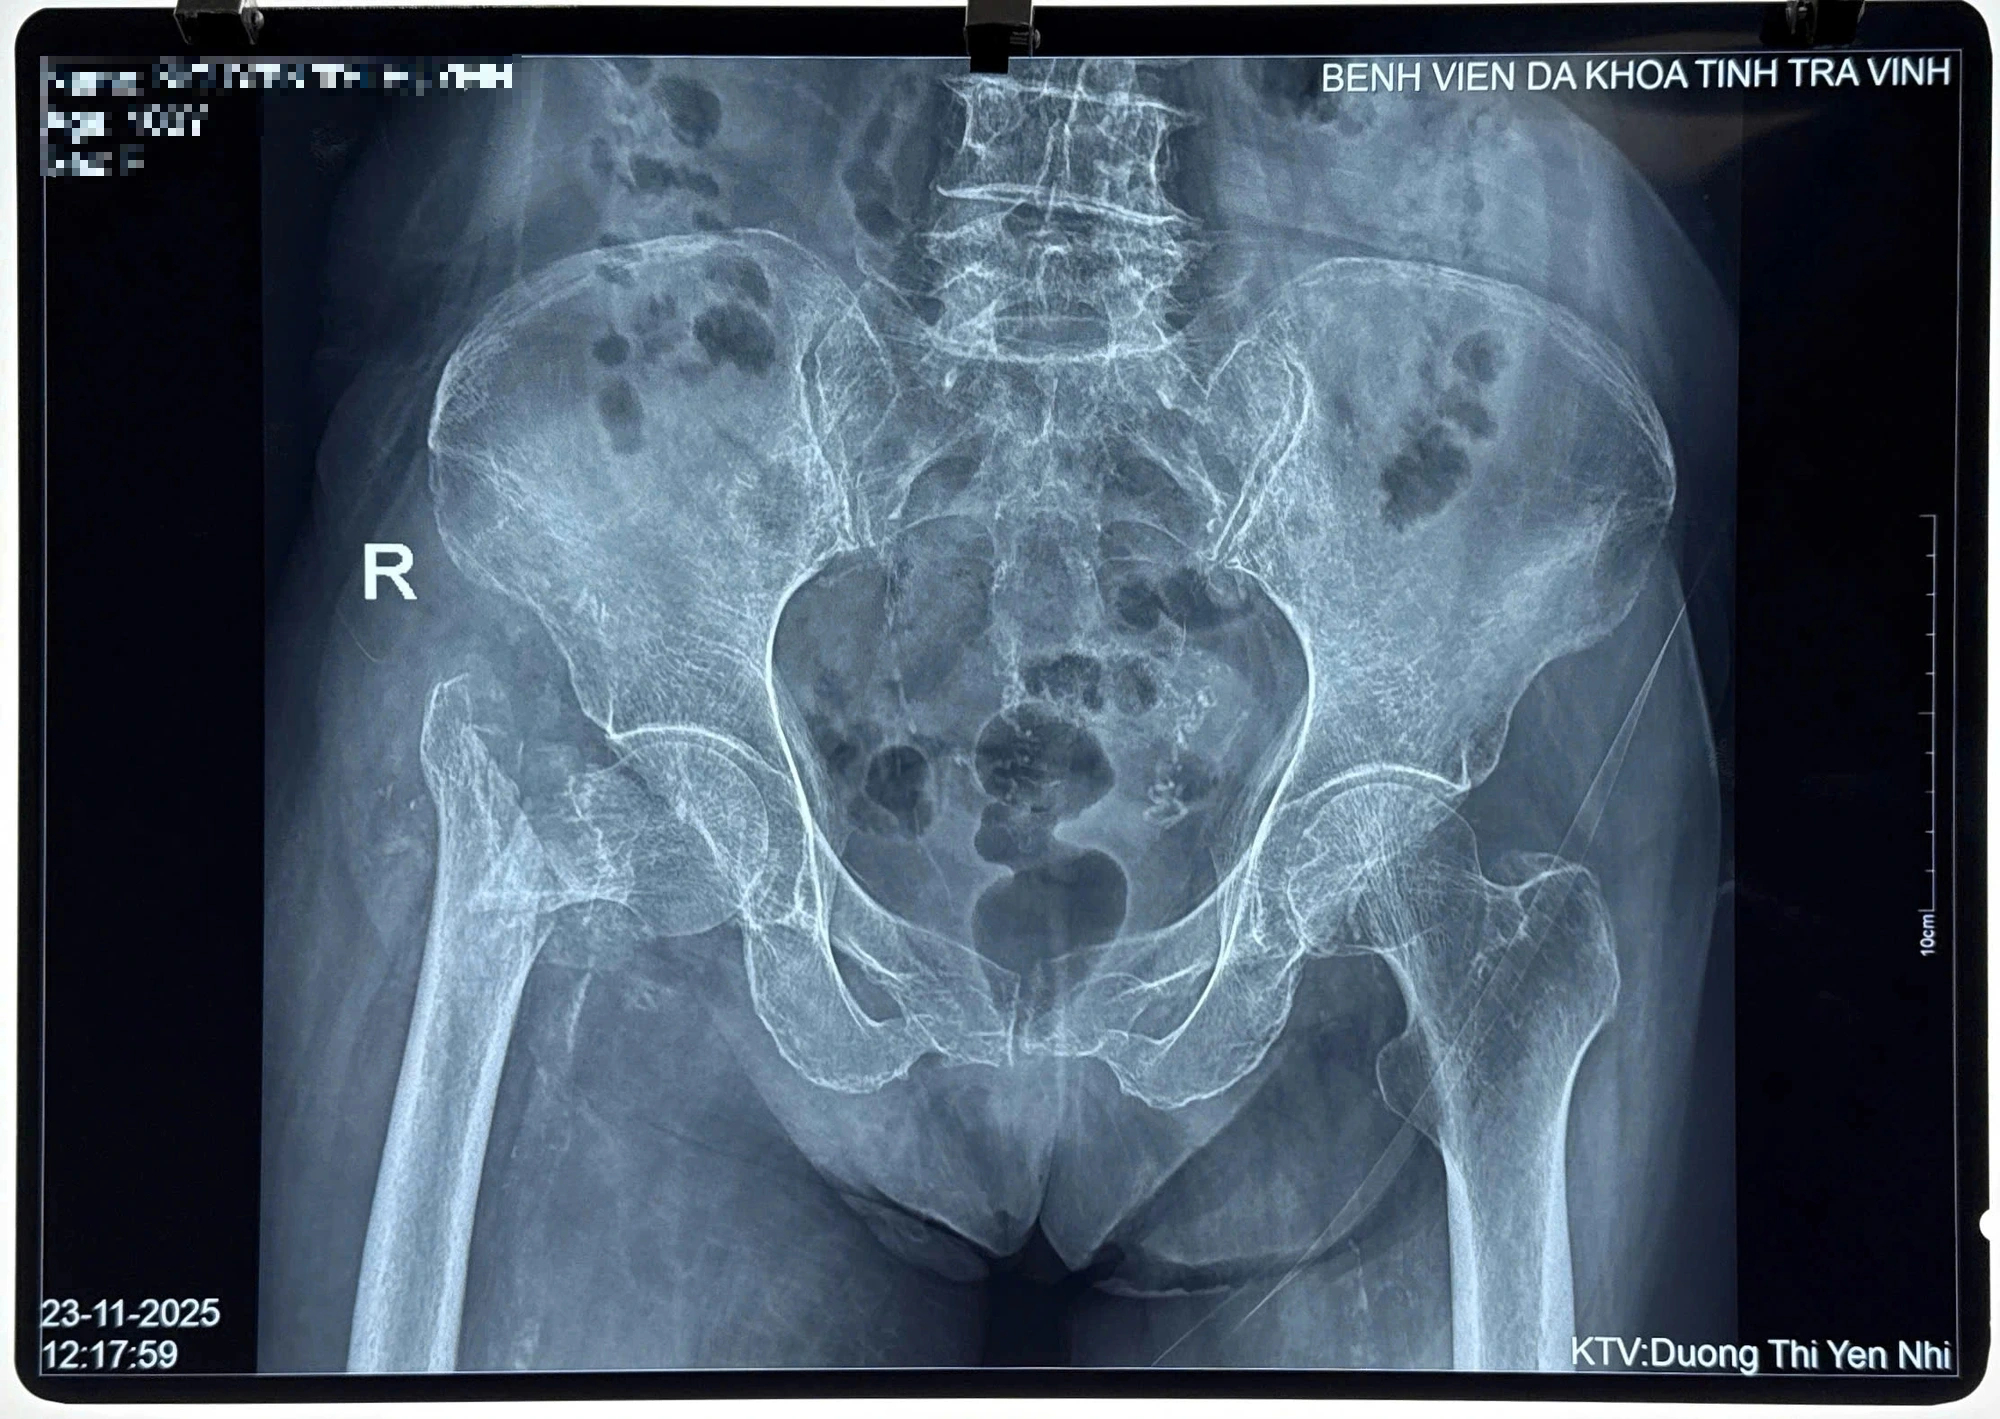

Trước đó, cụ N.T.H (100 tuổi, ngụ xã Bình Phú, Vĩnh Long) nhập viện do tai nạn sinh hoạt tại nhà. Qua thăm khám, chụp X-quang, các bác sĩ Khoa Chấn thương chỉnh hình của bệnh viện chẩn đoán bệnh nhân bị gãy nhiều mảnh đầu trên xương đùi bên phải, kèm loãng xương nặng, lão suy, viêm phổi, di chứng tai biến mạch máu não.

Hình ảnh X-quang chấn thương của cụ bà N.T.H trước khi được phẫu thuật

ẢNH: NAM LONG